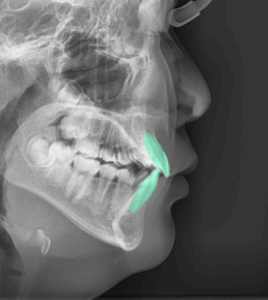

영구치 덧니 미니스크류 를 활용한 비발치 옥니 교정, 클리피씨 브라켓 활용 케이스

「 옥니란? 」 이가 혀 쪽으로 과도하게 기울어져 있는 상태를 일컫습니다. ​ 단순 비율로 보면 뻐드렁니가 더 흔하지만, II 급 부정교합 환자들 중에서는 옥니를 가진 사례도 종종 발견됩니다. ​ 발치…